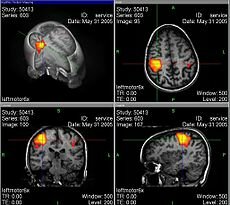

RESONACIA MAGNÉTICA

Demostró que la resonancia magnética podía ser usada para detectar enfermedades porque distintos tipos de tejidos emiten señales que varían en su duración, en respuesta al campo magnético.

Desarrolló la técnica para generar las primeras imágenes en resonancia magnética en 2 y 3 dimensiones.